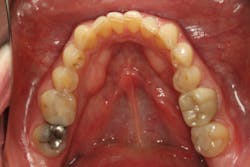

From the two-dimensional evaluation, the signs of occlusal instability were clear. Darren had very thin, chipping incisal edges, to the point where they were becoming transparent. The patient had almost worn shelves into the lingual of the maxillary anteriors, suggesting a restricted envelope of function. He also had wear into dentin in the anterior teeth as well as posterior teeth, and his anterior teeth had Class 1 mobility.

In addition, Darren failed The Dawson Academy’s five requirements of occlusal stability:

- Stable and equal intensity stops on all teeth in centric relation

- Anterior guidance in harmony with the envelope of function

- All posterior teeth disclude during mandibular protrusive movement

- All posterior teeth disclude on the nonworking side during mandibular lateral movement

- All posterior teeth disclude on the working side during mandibular lateral movement

Luckily, the patient was a Piper TMJ Classification 1 with healthy intact joint assembly. His functional problems were primarily occlusal-muscle. But the dentition also exhibited signs of acid corrosion in a presentation that suggested gastroesophageal reflux disease (GERD), so we referred Darren to his physician where he was treated for GERD prior to starting any dental treatment.